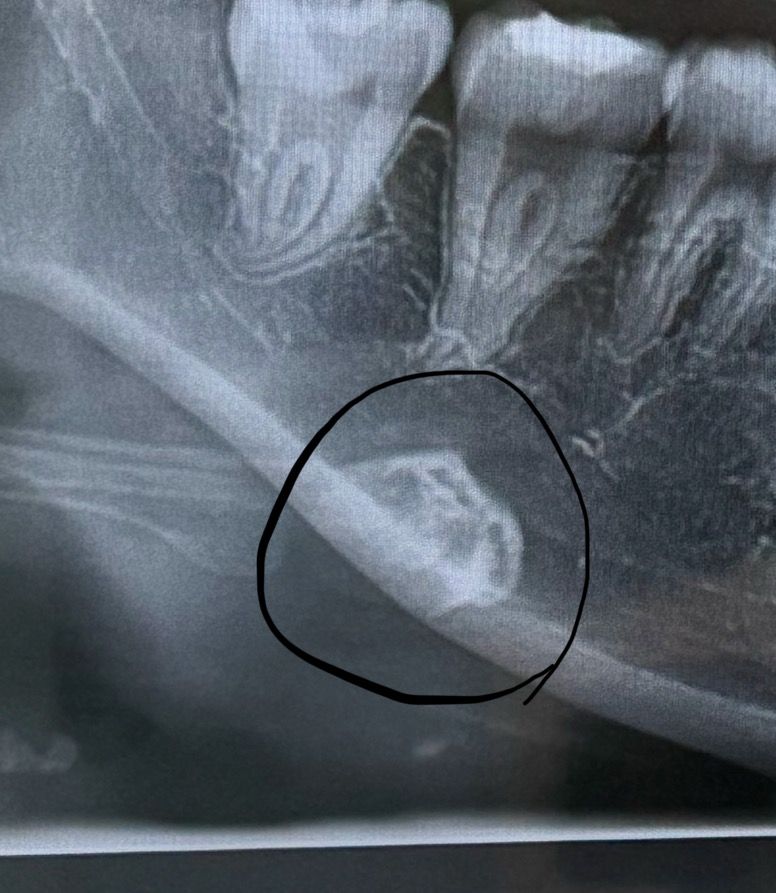

치아 파노라마 사진에 이 뼈 뭔가요??

치아 엑스레이 찍었다가 발견했어용 양옆 똑같은 자리에 있는데 이 뼈 뭔지 궁금해요...!!!!!!!!!!!!!!!!!!

사진에 보이는 구조물은 hyoid bone이라는 구조물로 설골이라고 불리는 구조물입니다.

설골로 보입니다. 누구나 가지고 있는 정상적인 뼈이며 엑스레이 각도상 그렇게 나오는 것 입니다.

Hyoid bone이라고 하는 설골입니다.

현재 저 사진은 아래턱뼈랑 겹쳐서 보이는 겁니다.

설골은 목부위에 위치하고 있습니다.

Hyoid bone(설골)로 파노라마 사진에서 종종 저렇게 턱뼈와 겹쳐보이기도 합니다.

사진을 목에 있는 뼈인 hyoid bone의 앞부분 입니다.

정상적으로 있는 구조물입니다.

파노라마 사진에서는 관찰하고자 하는 것 뿐만 아니라 다양한 해부학적 구조가 나타납니다. 저건 목뿔뼈, hyoid bone 입니다.